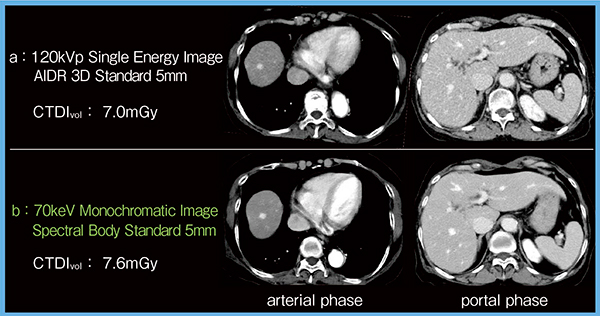

2.臨床データ

図2は,肝臓がん症例をほぼ同線量で撮影した120kVp画像(a)と70keV Mono画像(b)であるが,動脈相では70keV Mono画像の方が多血性腫瘍の辺縁がより明瞭である(b左)。これは,70keV Mono画像の優れた解像特性が反映されているためと考えられる。門脈相においても70keV Mono画像の方がノイズがより細かく,肝実質や脈管が観察しやすい(図2 b右)。

図2 ほぼ同線量で撮影した120keV画像と70keV Mono画像の比較